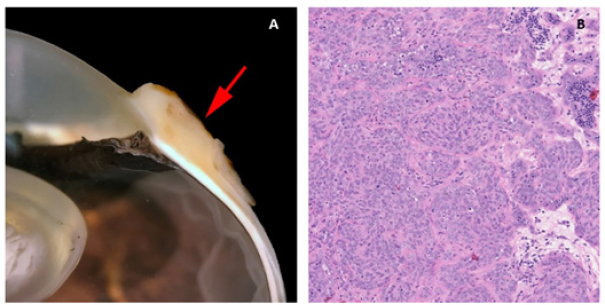

In the five horses diagnosed with conjunctival haemangiosarcoma, the histopathology findings confirmed the presence of a clearly vasoformative neoplasm in each case with the neoplastic endothelial cells either lining blood-filled vascular channels and/or forming solid nests (Fig. 3). Multiple lymphonodular aggregates or lymphoid follicles were commonly interspersed throughout the neoplastic infiltrate.

Fig. 3. H&E photomicrograph (400× magnification) of case 1 conjunctival haemangiosarcoma from the third eyelid of a horse. Irregular blood-filled vascular channels (star) formed by the tumour and lined by pleomorphic neoplastic endothelial cells (arrows).